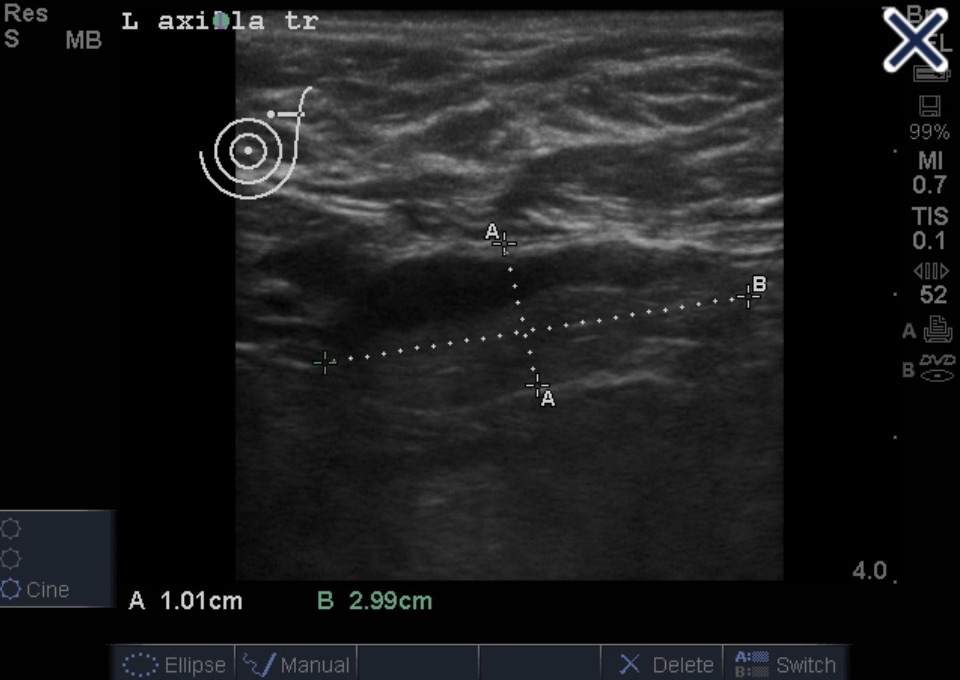

Ultrasound Appearance of Axillary Lymph Nodes

Abnormal lymph node with eccentric cortical thickening

• This axilla ultrasound shows a case of severe eccentric compression and displacement of the hilum to the edge of the node:

• Favoring metastatic disease

Severe eccentric compression and displacement of the hilum to the edge of the node.